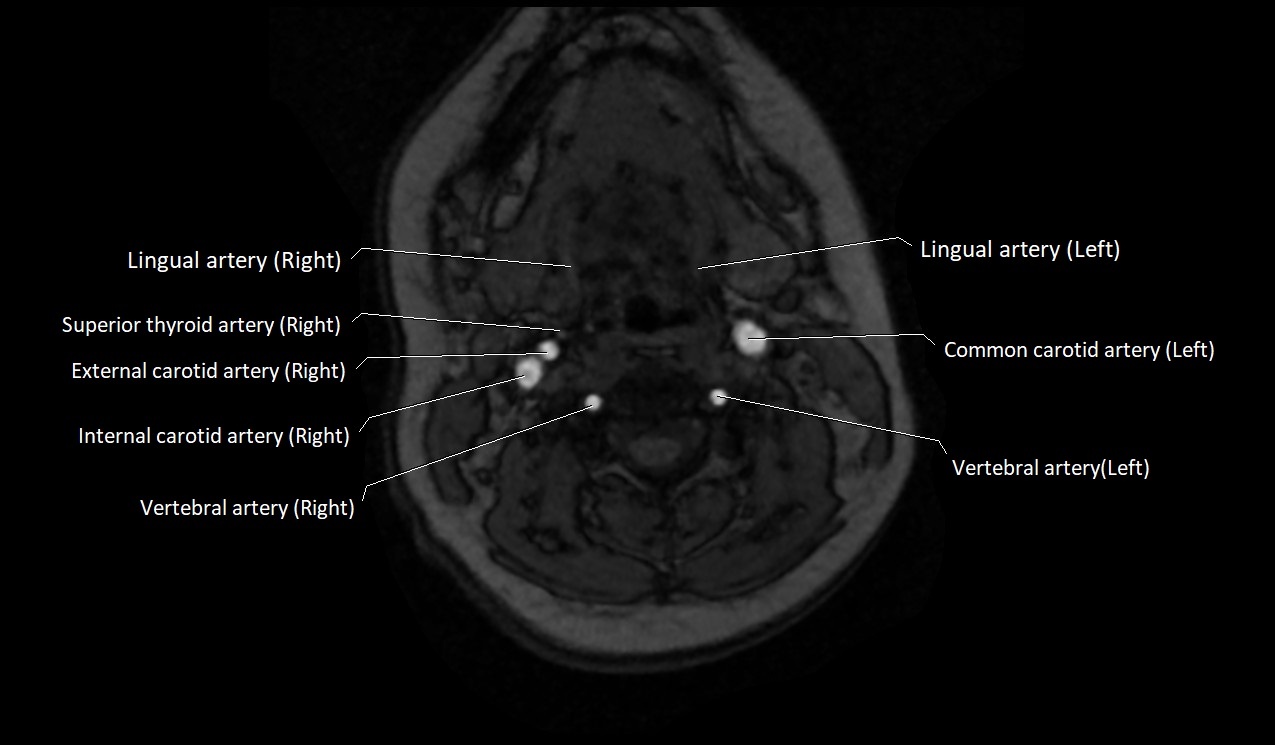

MRI images

image